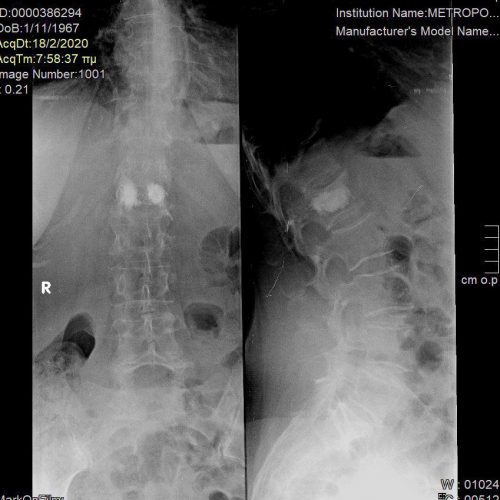

Με τη σπονδυλοπλαστική, εγχύεται ένα μίγμα οστικού «τσιμέντου» στον σπόνδυλο, προκειμένω να τον ισχυροποιήσει. Η διαφορά με την κυφοπλαστική είναι ότι στην κυφοπλαστική χρησιμοποιείται πρίν την έγχυση του τσιμέντου ένα μπαλόνι, το οποίο φουσκώνει μέσα στον σπόνδυλο, προκειμένω να αποκατασταθεί το ύψος και το σχήμα του σπονδύλου (Εικόνα 1 και 2).